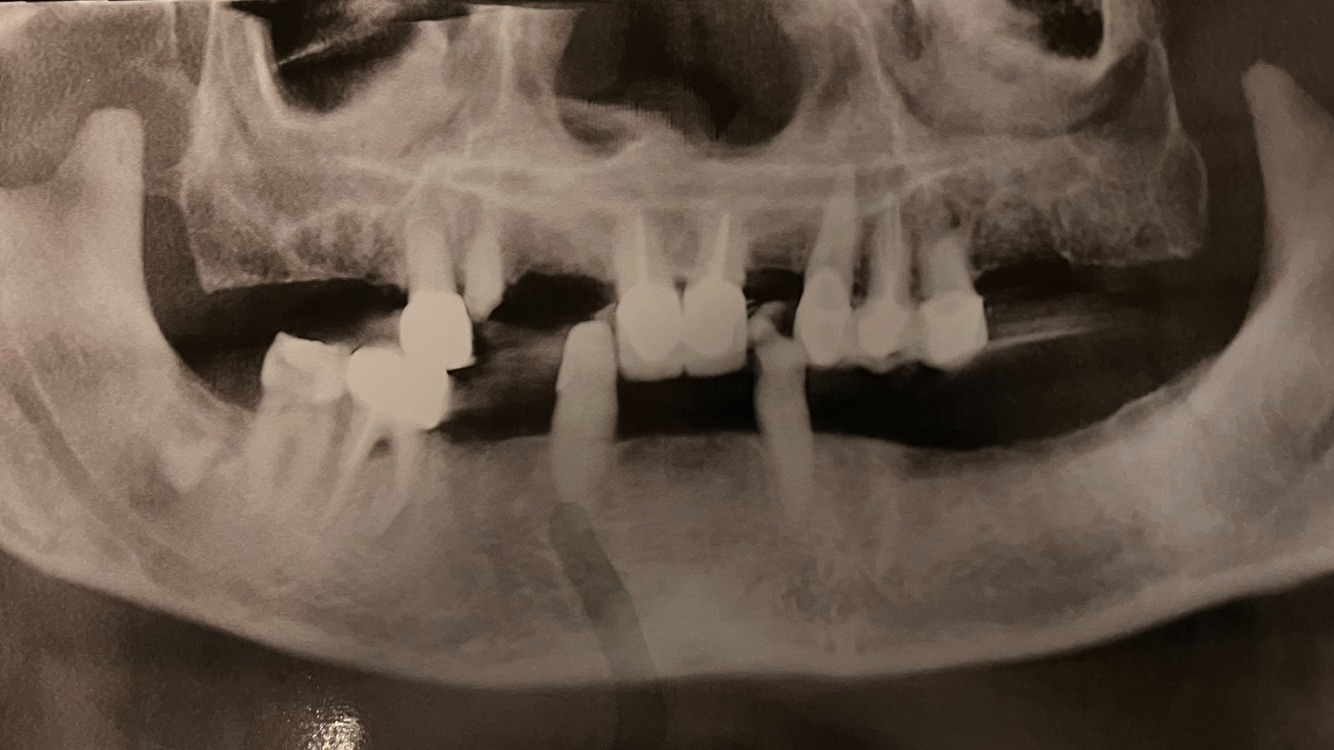

I wanted to update the main fundraiser page to say thank you to all the lovely folks who have donated and helped me bravely undergo the necessary surgery, and the tedious process of correctly fitting a full upper denture, and a significant lower partial denture (the two canine teeth on the bottom are still my own) It’s been months since we began fundraising, and at the same time scheduling the extractions, and appointments for the dentist to take impressions of my bite (pre-surgical extractions, and post surgical extractions). The first lower partial broke on day one, so we had to do another impression and send that to the lab. Now here we are. We’ve raised over $8,500 and I now have a full upper denture that fits well, and a lower partial that, we’re still making adjustments to to get it to fit better. For that I am beyond grateful. I feel like I owe a cosmic debt to the universe for the way this all worked out!